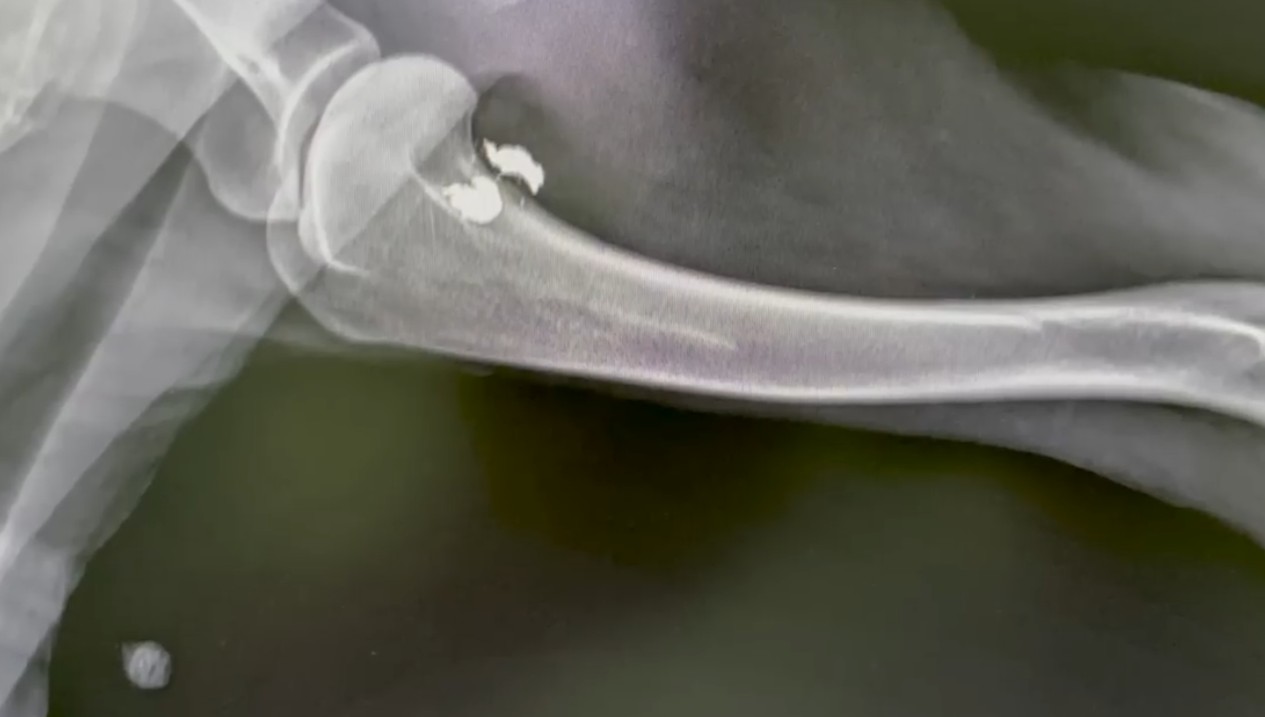

But the X-rays revealed the darkest truth of all. Inside her fragile body, doctors found two shotgun pellets.

Elsa hadn’t just been abandoned. She had been targeted. Someone had looked at this frightened, helpless creature and pulled the trigger, using her for target practice before leaving her to bleed out in the wilderness.